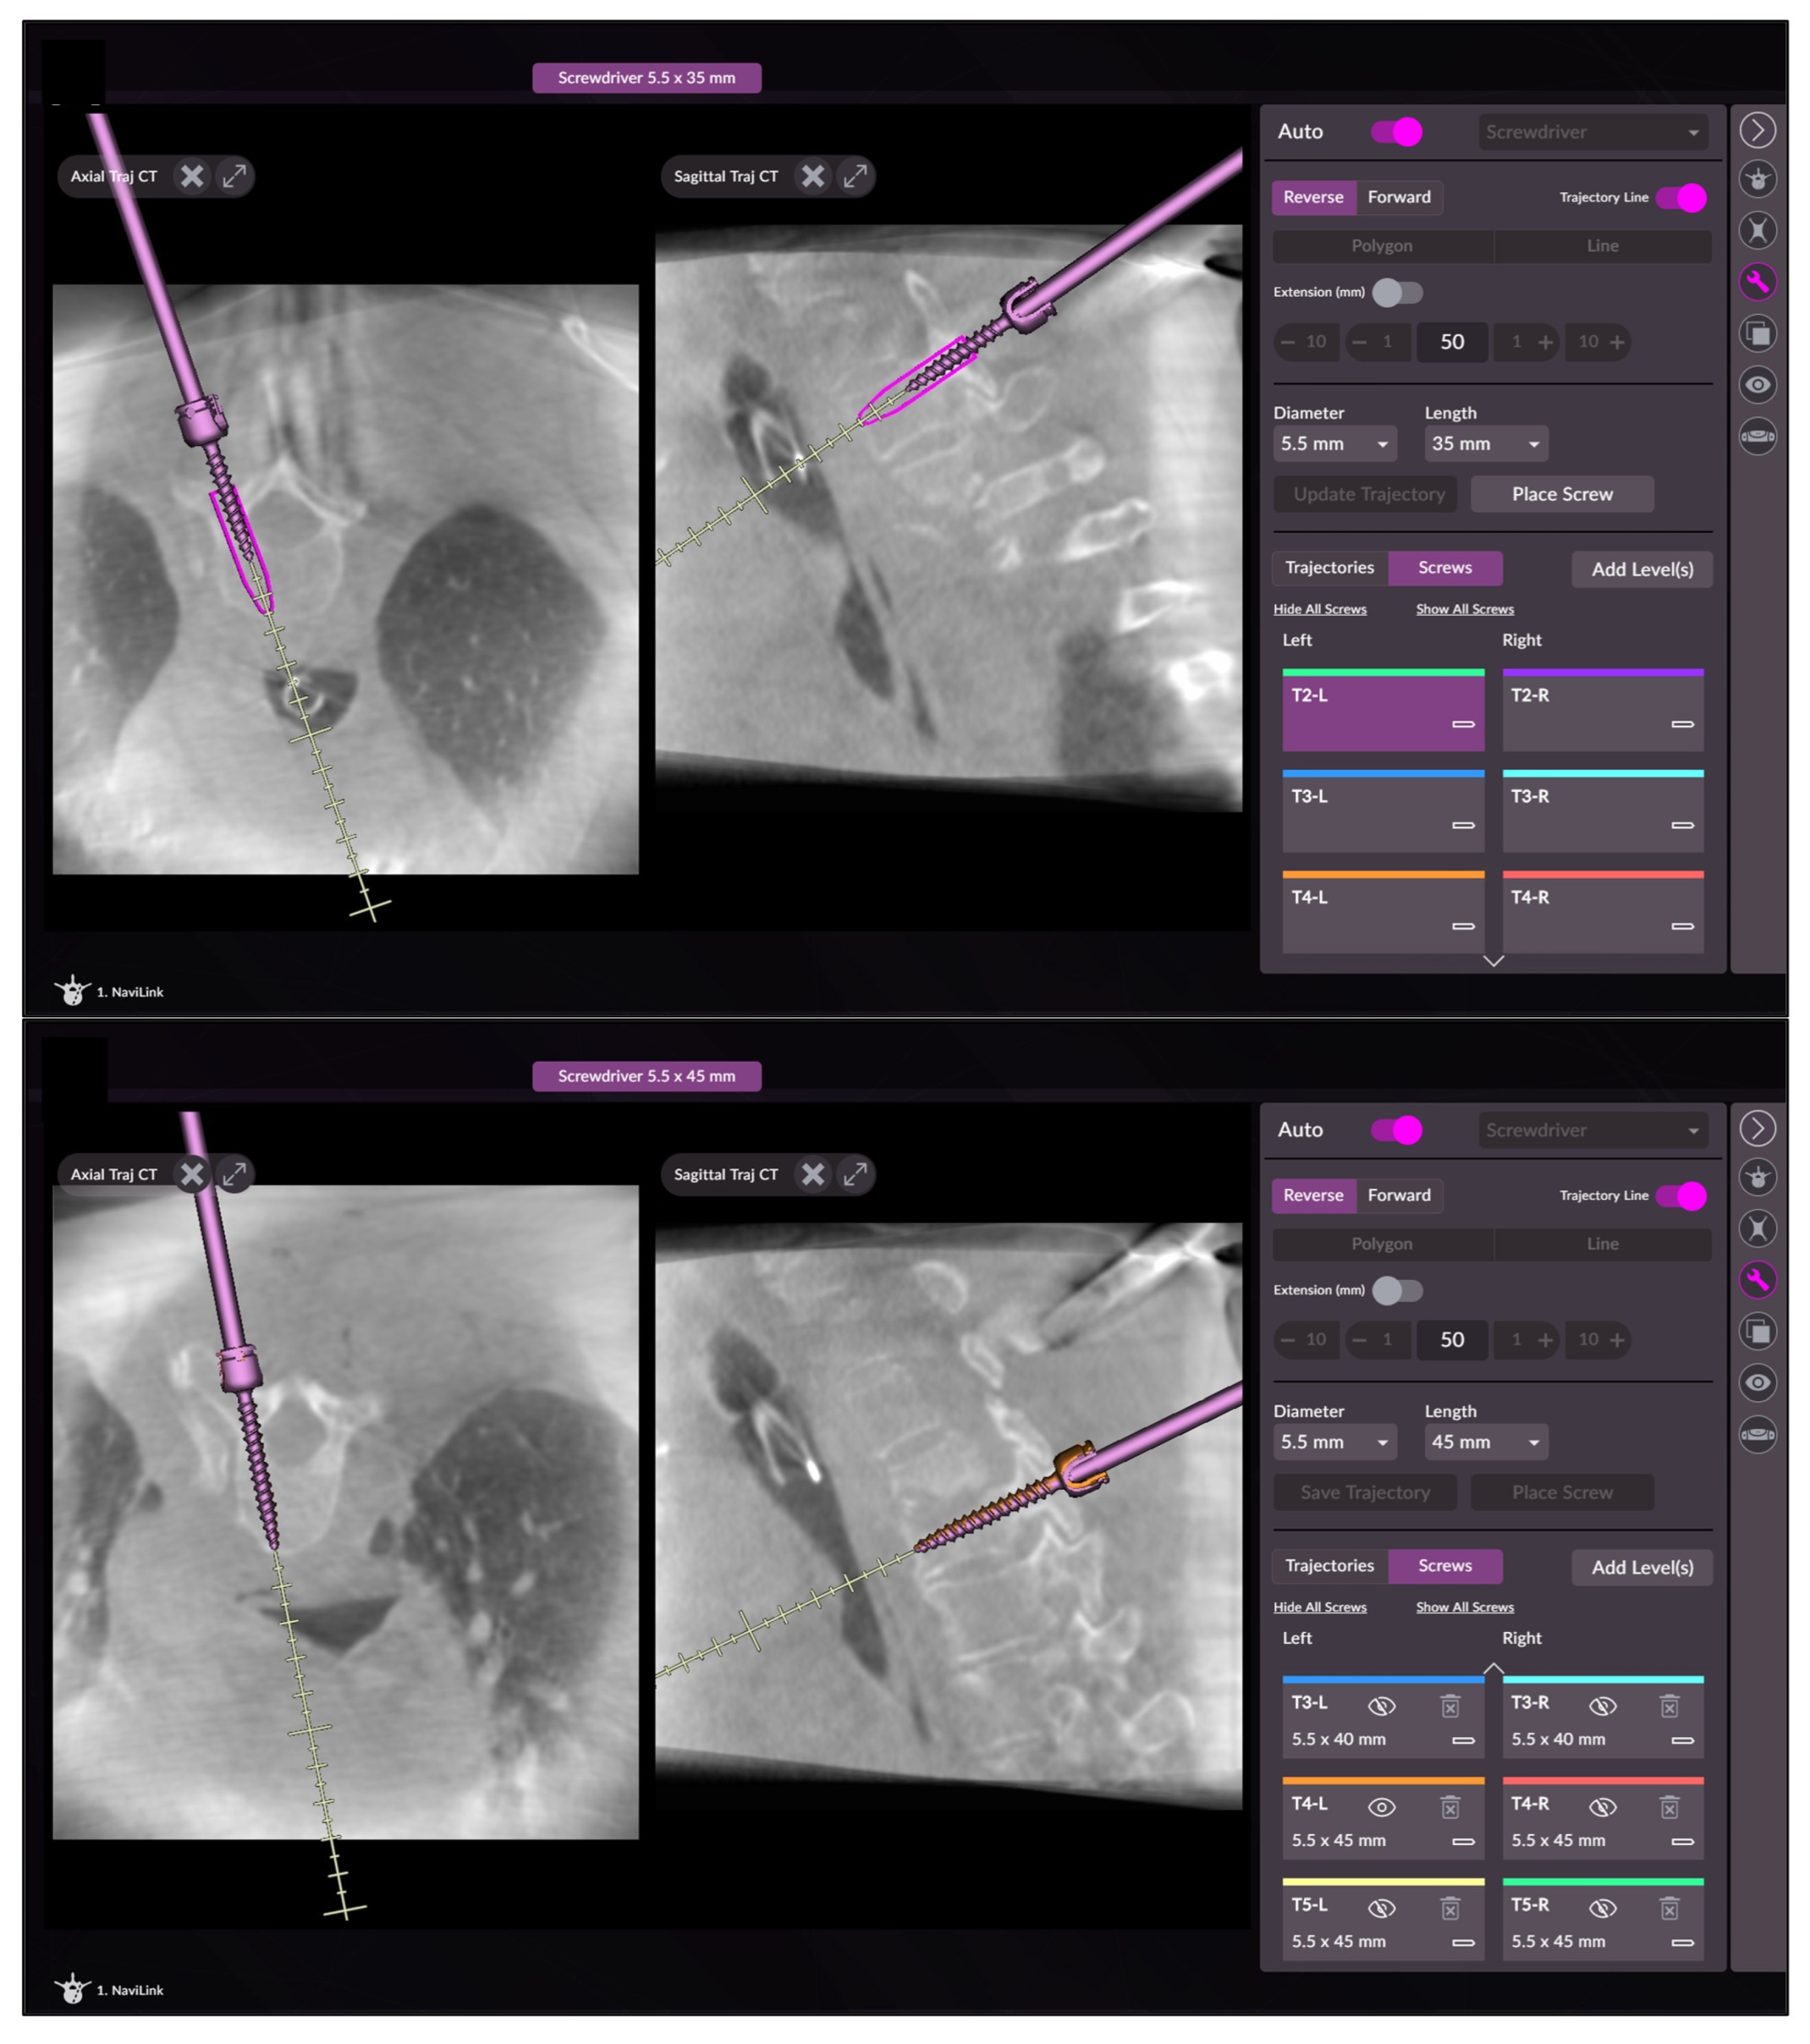

The guide wire also facilitates locating the exact entry point for the cannulated screw (Reline MAS, NuVasive, San Diego, CA, USA), which is then inserted according to the drilled trajectory continuously visualized in axial and sagittal planes on the screen (Figure 3). After screw placement is completed, standard fluoroscopic views are performed. In certain cases, an intraoperative 3D scan to analyze final screw position may be performed, in order to allow intraoperative revision of misplaced screws.

Figure 3. Screenshots of the navigation software during screw insertion with visualization of the planned position of the screw and with the correctly positioned screw.